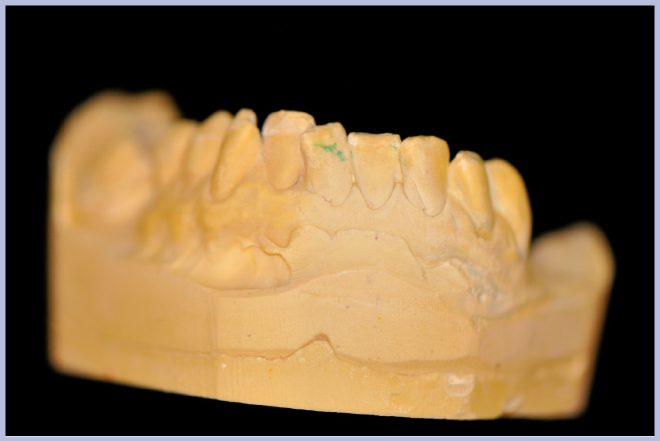

- Figg. 4, 5 – Realizzazione della mascherina radiologica

- Fig. 5